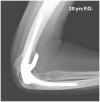

Anteroposterior radiograph 20 years after a Coonrad–Morrey elbow arthroplasty was implanted in a patient with rheumatoid arthritis.